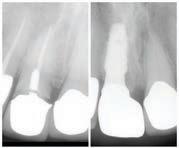

๊ฑด๊ฐํ ๋ฏธ์, ํดํผ์ค๋ง์ผ ์น๊ณผ์์

์ต์ ์ฅ๋น์ ์น์ ํ ์ง๋ฃ, ์ํ๋ํธ๊น์ง ๋ฏฟ๊ณ ๋งก๊ธฐ์ธ์!

ํนํ ํดํผ์ค๋ง์ผ ์น๊ณผ๋ ์ํ๋ํธ ์น๋ฃ

์ ๊ฐํ ์์ ๊ฐ์ ๊ฐ์ง๊ณ ์๋๋ฐ, ์์์

์น์ ๋ ์ฌ์ฉํ๋ ํ, ์ฆ ์น์์ ํฑ ๊ทผ์ก

์ ์ฌ์ฉํ์ฌ ์์์ ์๊ฒ ๋ถ์๋ ๋ฅ๋ ฅ๊ณผ

์ฌ๋ฏธ์ฑ์ ๋์์ ๋ง์กฑ์ํค๋ ์ํ๋ํธ๋

์์ฐ ์น์์ ๊ฐ์ฅ ๊ฐ๊น์ด ๋์ฒด ์น๋ฃ๋ก, ํ

๋์ ๋นํด ๋ ๋จ๋จํ๊ณ ์ค๋ ์ฌ์ฉํ ์ ์

์ธ์ ์น์๋ฅผ ๊น์ ํ์๊ฐ ์์ด ๊ตฌ๊ฐ ๊ฑด๊ฐ์ ์ ์งํ๋ ๋ฐ๋ ๋์์ด ๋๋ค. ํดํผ์ค๋ง์ผ ์น๊ณผ๋ ๋ณต์กํ ๊ตฌ๊ฐ์ธ๊ณผ ์์ ๊ณผ ์ง๋จ์ ์ํด ์น๊ณผ์ ์ฉ 3D CT ์ค์บ๋๋ฅผ ๊ฐ์ถ๊ณ ์์ผ๋ฉฐ, ์ด๋ฅผ ํตํด ์ ํํ๊ณ ์์ ํ ์ํ๋

ํธ ์์ ์ด ๊ฐ๋ฅํ๋ค. ํฑ๋ผ ์ํ, ์ ๊ฒฝ ์์น, ๋ผ์ ๋ฐ๋๊น์ง ์ ๋ฐํ๊ฒ ๋ถ

์ํ์ฌ ํ์ ๊ฐ๊ฐ์ธ์๊ฒ ์ต์ ํ๋ ์น๋ฃ ๊ณํ์ ์๋ฆฝํด๋๋ฆฐ๋ค.

๋ฟ๋ง ์๋๋ผ, ์ฌ๋ฏธ๋ณด์ฒ ๊ณผ ๋ฏธ์ฉ์น๋ฃ, ์ผ๋ฐ์น๊ณผ, ์์์น๊ณผ, ๊ตฌ๊ฐ์ธ๊ณผ, ์ ๊ฒฝ

์น๊ณผ ๋ฑ ๋ค์ํ ๋ถ์ผ์ ์ ๋ฌธ ์๋ฃ์ง์ด ํจ๊ปํด ํ ํ ์น๊ณผ ์ง๋ฃ๋ฅผ ์์คํฑ ์ผ๋ก ์ ๊ณตํ๊ณ ์๋ค.

ํดํผ์ค๋ง์ผ ์น๊ณผ์์๋ ์ ํธ๋(Aetna), ์ค์ฌ(Anthem), ํด๋ ๋ฒ์ผ์ด (Clever Care), ์์คํฐ๋ฐ(Astiva), ํด๋จธ๋(Humana), ๋ฆฌ๋ฒํฐ(Liberty), ์ ๋ ์ดํฐ๋ํฌ์ค์ผ์ด(United Healthcare) ๋ฑ. ๋ค์ํ ๋ณดํ์ ์ทจ๊ธํ๊ณ ์๊ณ , ๋ฉ๋์นผ/๋ฉ๋์ผ์ด PPO ๋ณดํ ํ์ํ๋ค.

์ข์ ์ฌ๋ฃ์ ๊ณ ํ์ง ์ง๋ฃ, ์ต์ ๊ธฐ์ , ๊ทธ๋ฆฌ๊ณ ํ์๋ฅผ ์๊ฐํ๋ ์ง์ฌ์ด ์๋ ํดํผ์ค๋ง์ผ ์น๊ณผ์์ ์จ ๊ฐ์กฑ์ ๊ฑด๊ฐํ ๋ฏธ์๋ฅผ ๋์ฐพ์๋ณด์.

๋ฌธ์ ๋ฐ ์์ฝ: 818-775-1200